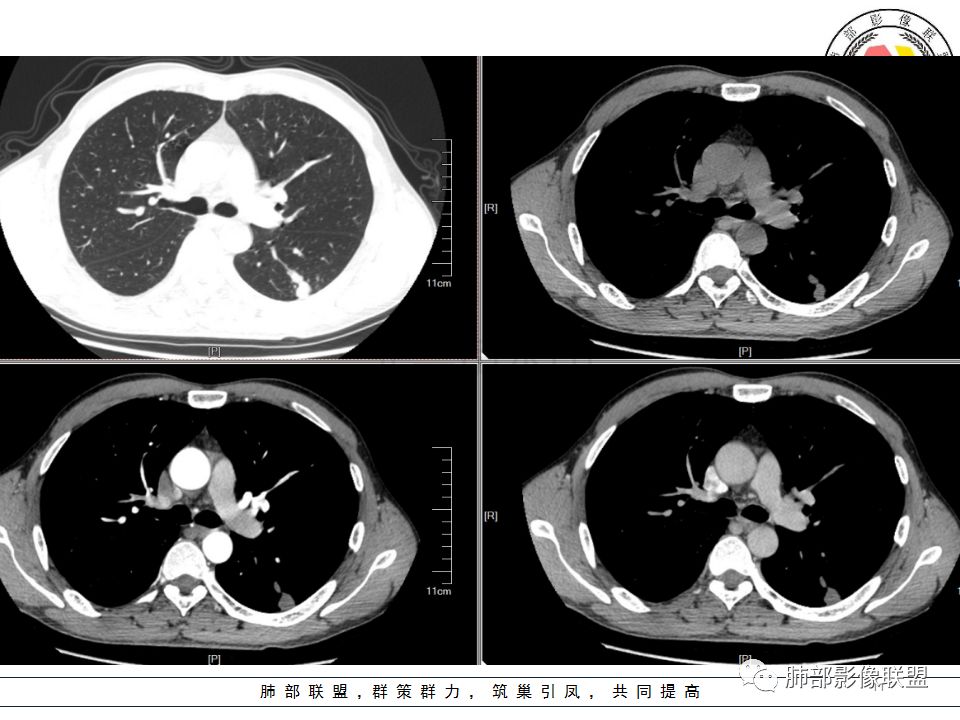

病历资料

左肺下叶背结节丶融合趋势,形态较单一,平直,无胸膜凹陷,目测轻强化,有支气管爬行丶子灶。诊断:TB>pC>腺癌。

左肺下叶结节,边缘平直为主,部分膨隆,卫星病灶,似乎无强化,糊墙,胸膜下脂肪间隙增宽,结核可能性大,腺癌待排。

左肺下叶背段孤立结节,长轴与胸膜平行,支气管近端截断,刀削平直,糊墙,卫星灶轻强化,考虑TB。

左肺下叶背段小结节 ,糊墙 ,胸膜外脂肪间隙增宽 ,引流支气管壁厚 ,有爬行征 ,病灶无明显强化,考虑结核可能。

病史:男,50岁,胸痛15天,无抽烟;胸膜下病灶,有可能相关;

影像:病灶不规则,形态奇特,矢状位可能看到病灶的真实形态;上面近端病灶似乎与主病灶不相连续,多病灶?内侧似乎小花小草,疑为卫星灶;胸膜下病变,与胸膜关系不密切,胸膜线状强化;强化方式渐进性,感觉不均匀,也许是伪影;病灶凹陷平直不膨隆,考虑良性。诊断:结核;鉴别:腺癌(近胸膜端三个胸膜反应凹,偏上部层面毛刺不能除外,但其他地方没有,整体收缩力还比较弱,无钙化,考虑没有形成钙化和纤维化。

男性,胸疼,左肺下叶背段结节,边缘光滑,有平直收缩,轻度延迟强化?胸膜肥厚,有轻度胸膜牵拉,周围有卫星灶,考虑炎性病变,结核,隐球可能性大。鉴别腺癌。

左肺下叶背段结节,边缘较光整,平直,近端支气管未见明确截断征象,沿支气管走行,临近胸膜局限性增厚,增强目测未见明确强化,周围见稀疏小树芽分布,整体考虑良性病变,结核放前考虑。

男,50岁,左肺下叶结节影,似乎两个结节,相邻,上面一个偏内,有分叶,下面一个偏外,胸膜下,内侧有稍增厚的支气管影,并且支气管进入病灶内,周围有更小卫星灶,外侧有胸膜增厚,糊墙。总的来说,考虑炎性病灶,结核可能性最大。但靠内侧的结节有恶性特征,腺癌待排。

50岁男性,吸烟,胸痛15天。左肺下叶胸膜下结节,边缘平直为主,部分膨隆,但似乎呈山丘,沿支气管爬行,周围是卫星灶还是小花小草,考虑恶性,小细胞癌可能性大,结核待排。

左肺下叶背段结节,边缘光滑,有平直收缩,强化不明显,胸膜肥厚,有轻度胸膜牵拉,周围有卫星灶,考虑感染性病变,结核首选。

左肺下叶背段结节,形态近似两个结节融合或靠近,沿支气管走行分布,近侧支气管内见条状软组织,增强未见明确强化,周围见小树芽,首先考虑结核,鉴别小。

患者中年男性,因胸痛半月入院。查血常规、凝血功能、肾功能正常。有抽烟史。胸部CT:左肺下叶背段胸膜下与胸膜垂直长条形不规则病灶,支气管爬行改变,边缘欠清楚,部分层面呈葫芦样见血管集束征、周围点状卫星灶,增强无明显强化,左肺门淋巴结肿大。综合常规结核可能性大,其次小细胞肺癌。鉴别其他。

左肺下叶病变,边缘平直,似有U形凹陷,树芽及卫星病灶,支气管爬行征?无明显强化,考虑结核。

左肺下叶背段近胸膜下结节,部分边缘平直并可见卫星灶,增强后强化不明显,首先考虑结核。

中年男性,左肺下叶背段结节,内可见支气管充气征,周围有晕,周围有结节,局部胸膜增厚,可见脂肪间隙。考虑良性病变可能,隐球?,鉴别结核;病灶有沿支气管生长趋势,气道阻塞,经皮肺穿除外肺癌。

中年男性,胸痛,吸烟史。左肺下叶背段结节,边界清楚,局部见小毛刺及胸膜牵拉,部分层面成葫芦形,局部与胸膜宽基底相贴,邻近胸膜增厚。近端支气管达病灶边缘处,似略增厚。周围见少量卫星微结节及树丫。增强扫描无强化。考虑:1,结核:支持点有发病部位,邻近卫星灶及树丫,近病灶边缘支气管壁似略增厚,邻近胸膜增厚。不支持点,引流支气管壁增厚范围不够长。2,小细胞癌:支持点有局部葫芦形,似沿支气管向肺门区扩展。3,腺癌:支持点有毛刺和胸膜牵拉,当然结核也可以有这两个征象。不支持点有无强化。